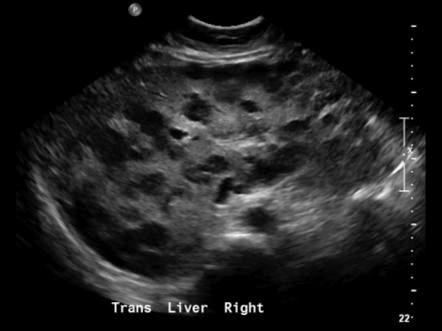

What is Cirrhosis?

A chronic degenerative disease in which there is parenchymal necrosis, regeneration and fibrous tissue resulting in disorganization of lobular architecture. Lobules are infiltrated with fat. Commonly caused by alcoholism.

What is the sonographic appearance of Cirrhosis?

Hepatomegaly

Increased echogenicity and attenuation

Size

decrease of right lobe

Size increase of left and caudate

lobe

Nodularity

Fibrosis

Hepatospenomegaly

Ascites

Portal

hypertension

Hepatoma tumors

caudate lobe may be spared